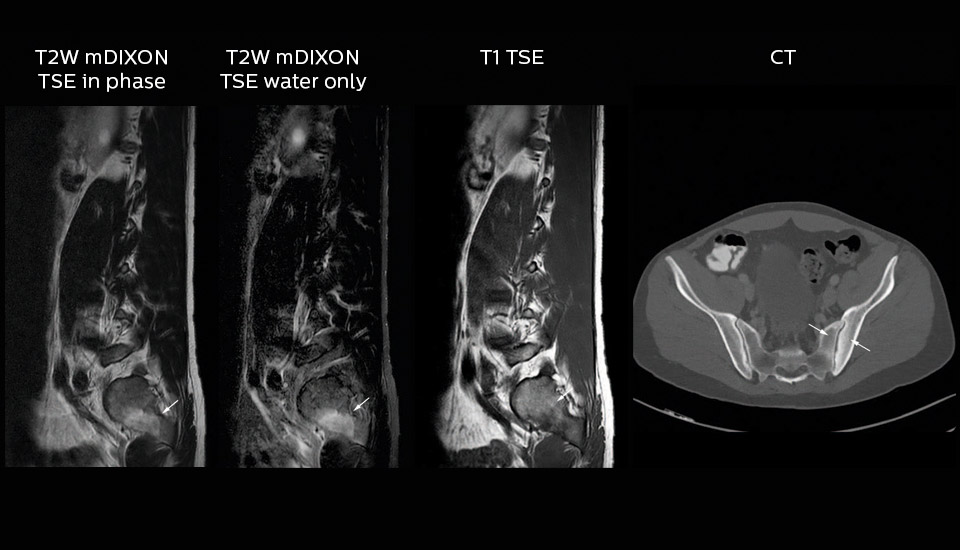

mDIXON TSE boosts homogeneity and efficiency

Dr. Heggelman raves about mDIXON TSE because it provides him an extra image series without having to add another scan.

“With mDIXON TSE, we not only get a T2-weighted series, but we also get the T2 fat suppressed images ‘for free’ in the same scan. I feel much more confident with the homogeneous fat suppression that mDIXON TSE provides under virtually all conditions, even in this challenging anatomy. SPAIR and SPIR weren’t good enough due to the susceptibility problems in the air cavities, so that fat suppression was not homogeneous over the whole field of view. That made it difficult to see whether something was enhancing or the fat suppression was not good enough.”

“To me the most remarkable fact is that mDIXON TSE provides us T2-weighted images with and without fat suppression at the same time. In the past we needed two separate sequences for that, so it does save some time.”

Value of mDIXON TSE image quality

“The excellent image quality of mDIXON helps us a lot. We can, for instance, see the foramina in the skull base very well. Also our confidence in imaging of the facial nerve and the trigeminal nerve is highly improved. Visualizing these nerves properly used to be difficult because they run very close to the air cavities. However, it is very important to know if there are abnormalities or not. I’m very satisfied with the possibilities of mDIXON TSE.”